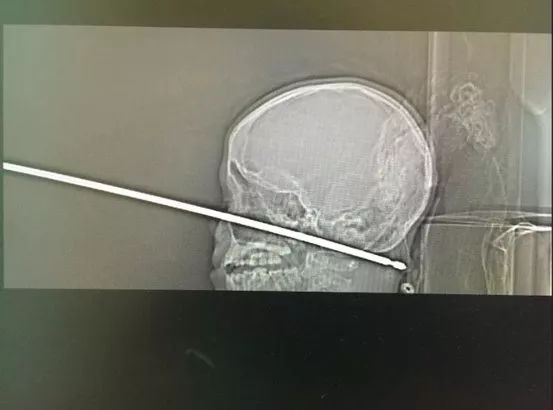

脑部被刺穿后仍奇迹活下来的男孩

Credit: Medical News Network/Cliff Erwin

据美媒KCTV5报道,密苏里州一10岁男孩正在玩耍时被黄蜂袭击,导致他从高处摔下来,并不幸地落到了放在地上的烤肉叉上。对男孩头部的扫描显示,肉串钎子刺穿了他的脸,正好穿过头骨下面,并一直延伸到脖子后面。幸运的是,串肉钎刚好错过了这个男孩儿的脑部关键结构(脑干,神经元)。之后通过小心翼翼的手术,医生们已将钎子取出,小男孩儿目前已恢复健康。